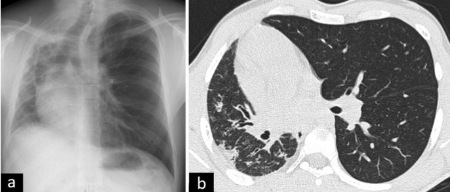

سونوگرافی جنین در هفته ۲۰ بارداری ابزار اصلی غربالگری است. پس از تولد، رادیوگرافی قفسه سینه ممکن است ناهنجاری را نشان دهد، اما سیتی اسکن با کنتراست استاندارد طلایی تشخیص است. این روش جزئیات آناتومیک، تأمین عروقی و ارتباط با درخت برونش را بهخوبی نشان میدهد. امآرآی در موارد پیچیده یا برای ارزیابی محتوای پروتئینی کیستها مفید است. برونکوسکوپی و آنژیوگرافی در موارد خاص کاربرد دارند.